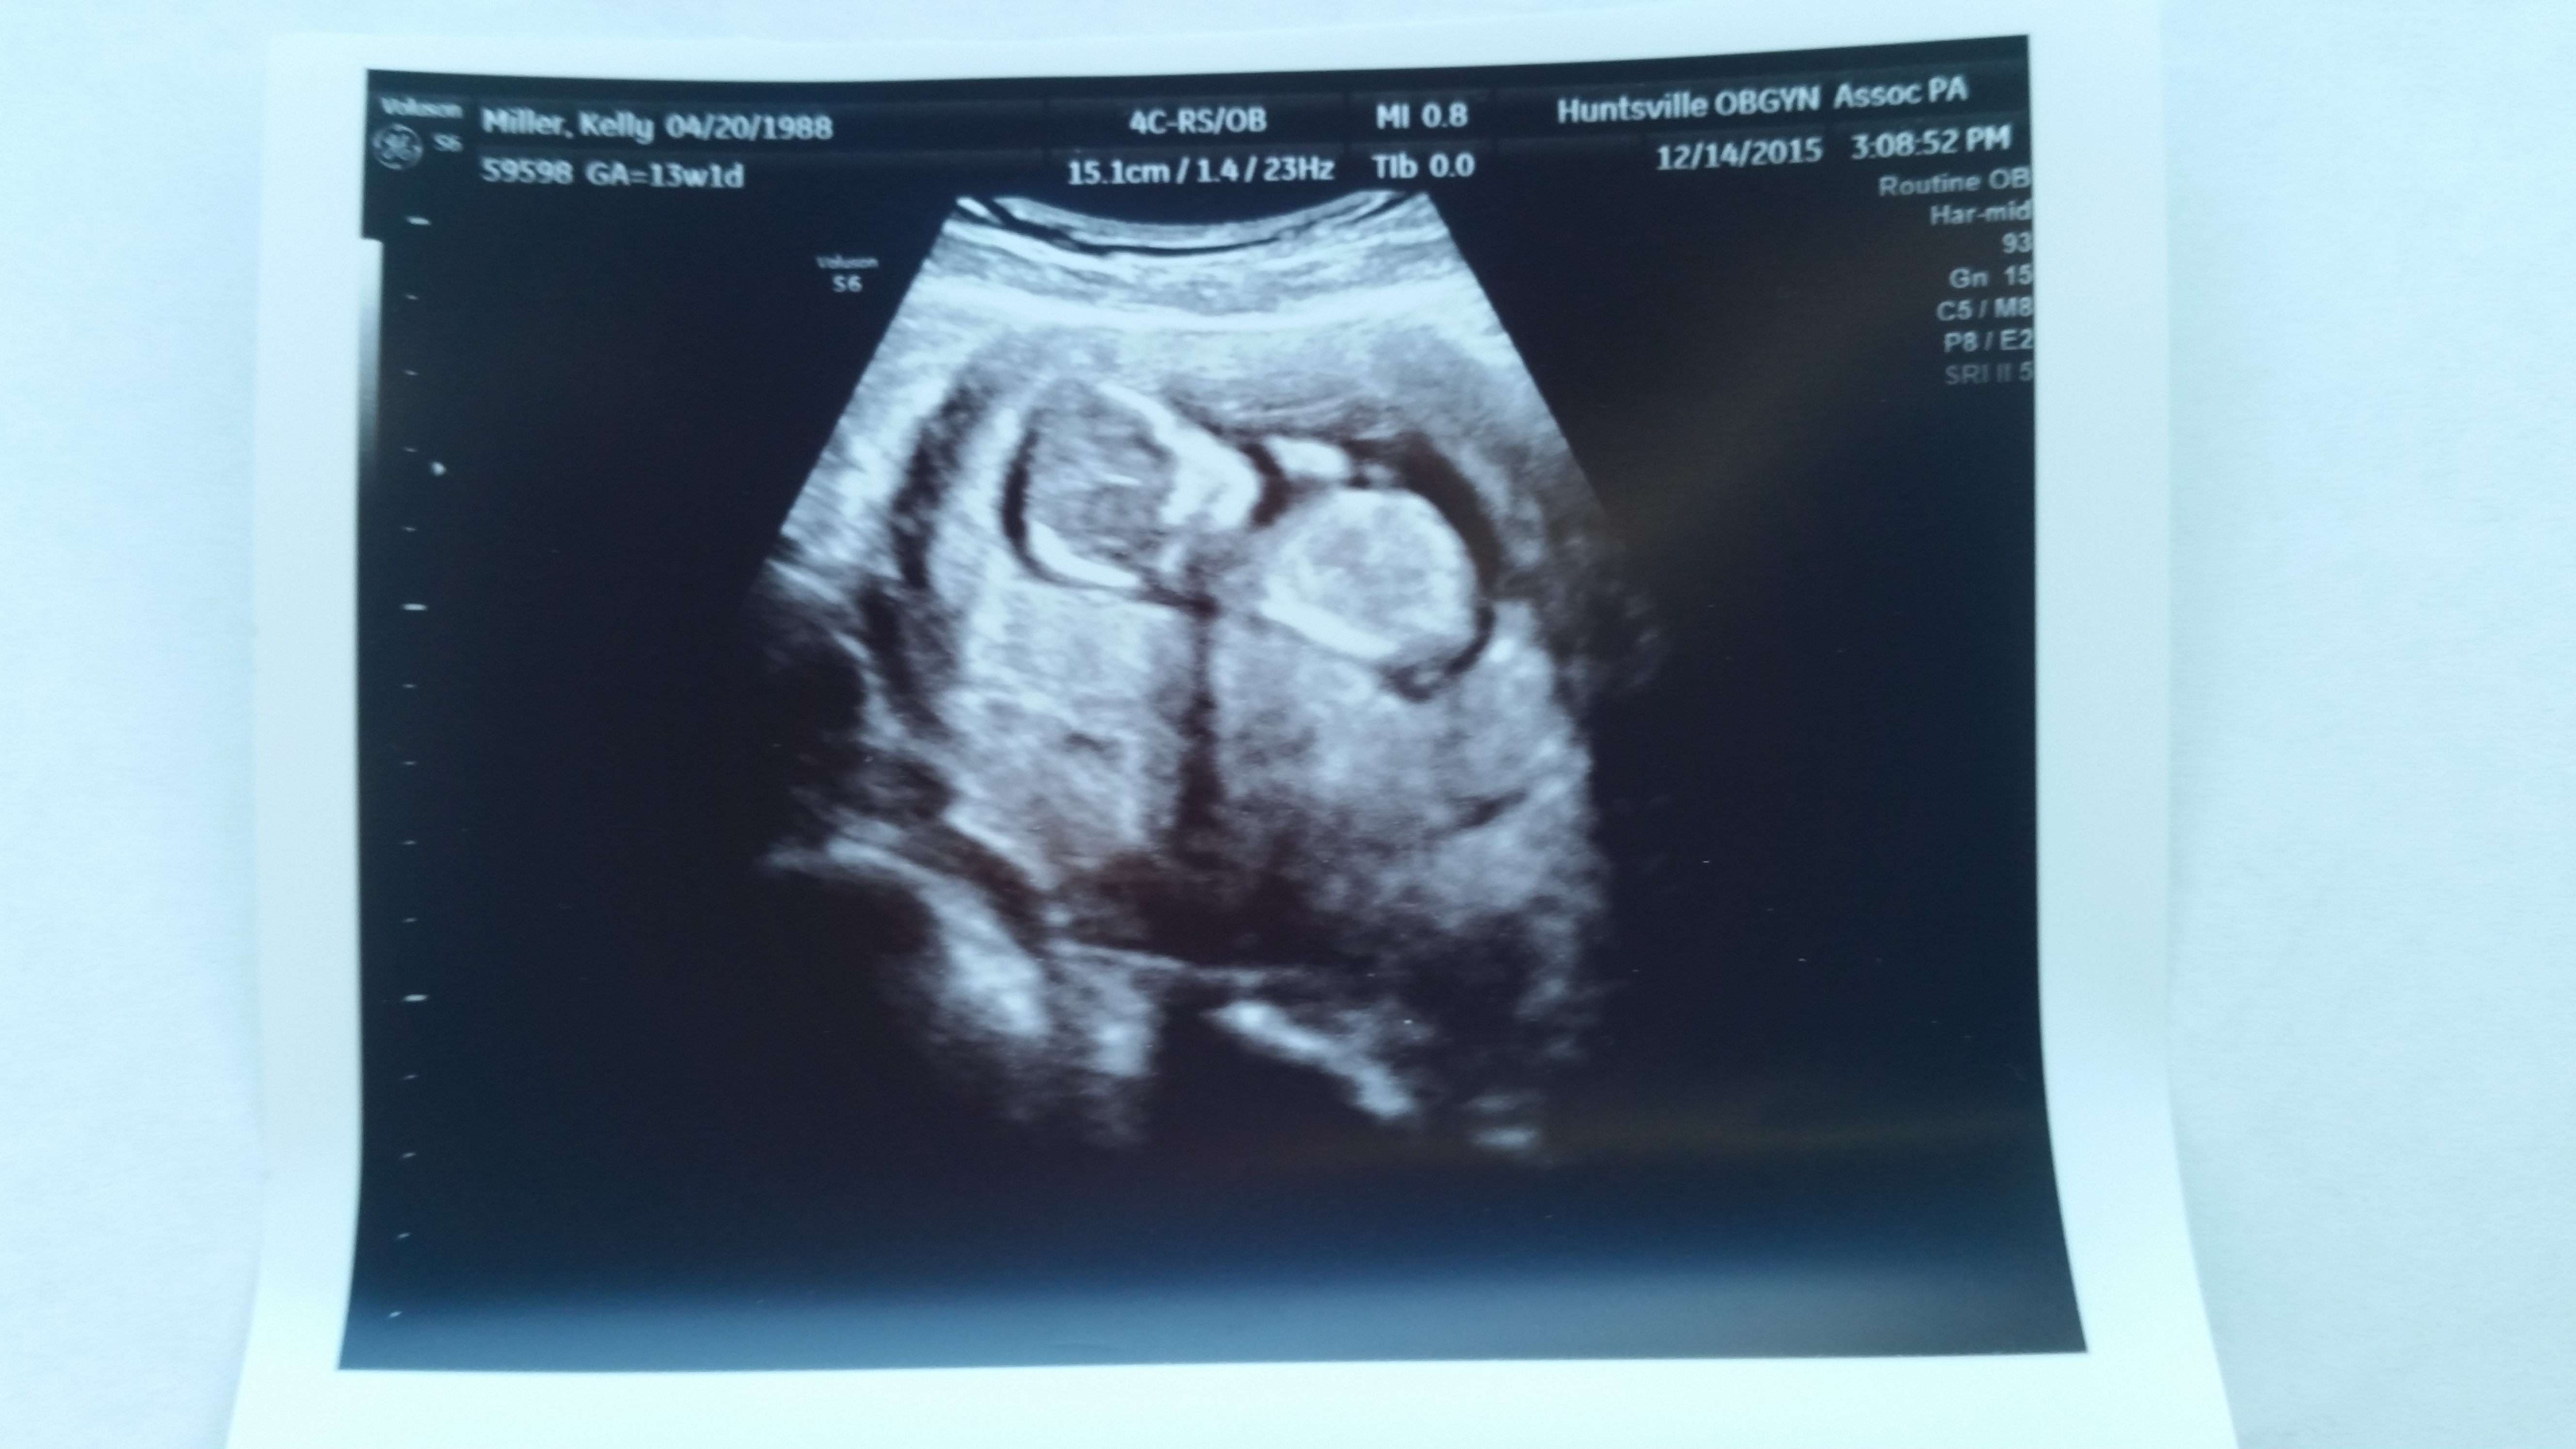

Had an unexpected drs appt monday. Had been having some cramping and spotting off and on since last friday. Turns out everything was fine. But got to see another pic of our baby. Otherwise we wouldn't he gotten another til 20 weeks. So glad that everything is ok, but off my feet til the spotting stops. This was at 13W1D.